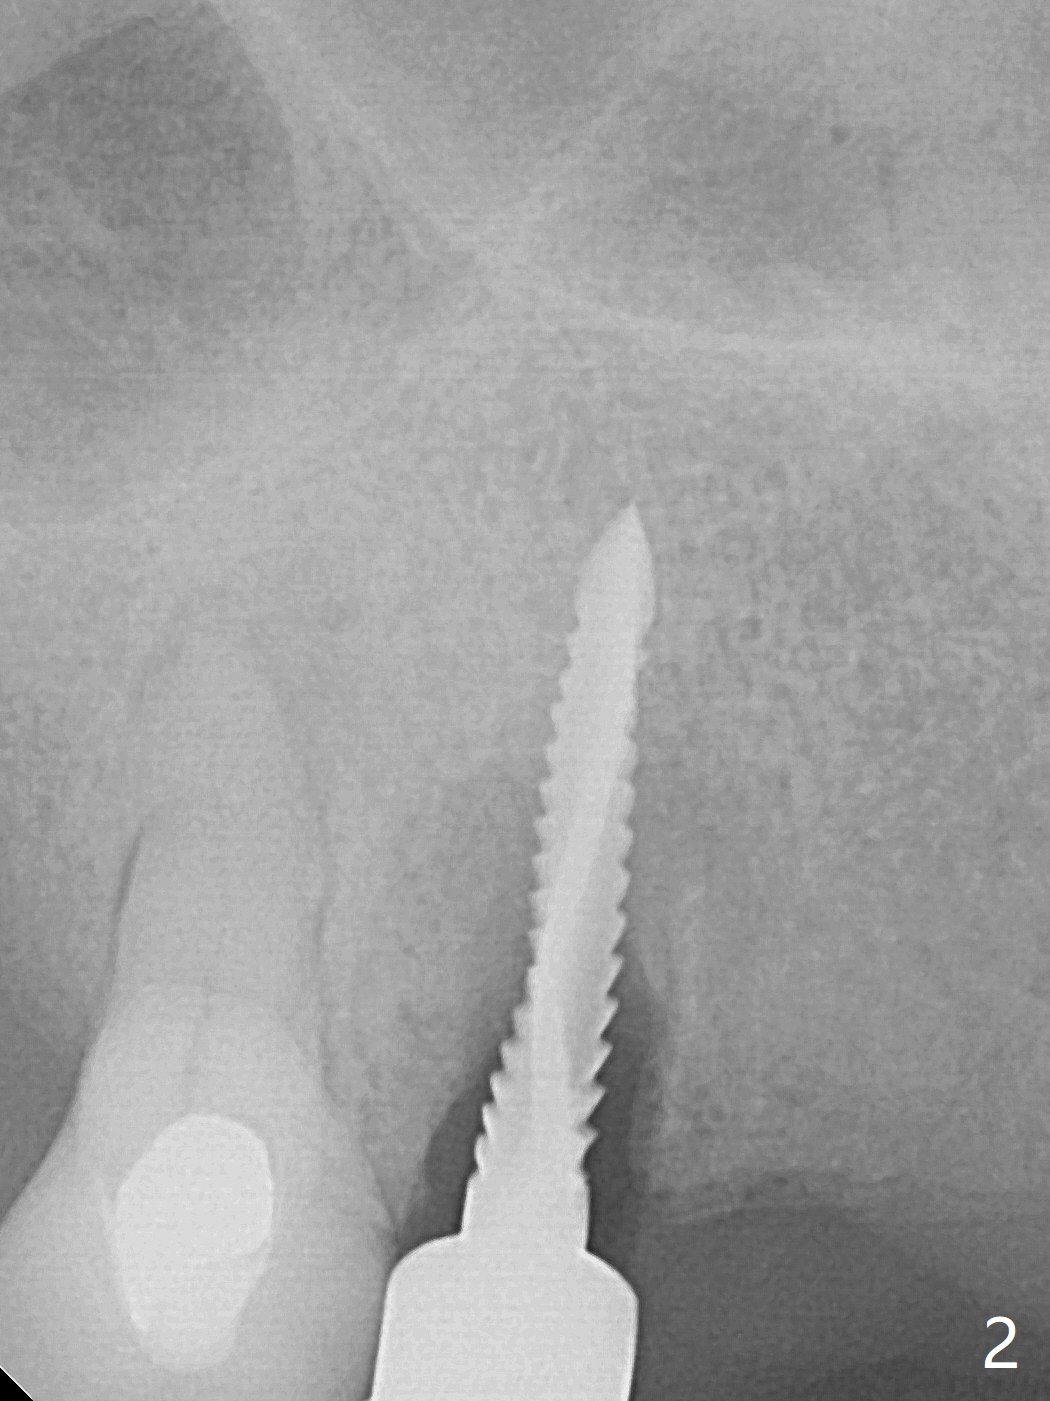

部分断裂的5号牙颊侧根尖有3个瘘道(图一),五类(颈部)缺损,严重牙龈退缩。牙齿拔除过程中断裂,需要手机切断拔除,颊侧骨板缺失,钻洞起源于牙槽窝腭侧(融合根,图二,五),植入4x13毫米长植体,根尖骨大约4毫米,植体也卡入近中,远中骨壁,扭力大于35Ncm,即刻放置基台,颊侧间隙(图三至五:*)放入粘性骨粉,牙槽窝口用PRF穿过基台关闭(图五),接着制作临时牙冠(图六:T),多次衬里严密关闭牙槽窝,而咬合面低,最后插入活动托牙(图七:RPD,左侧有两个基牙)。Return to Protect Graft Torque Xin Wei, DDS, PhD, MS 1st edition 05/18/2021, last revision 05/18/2021